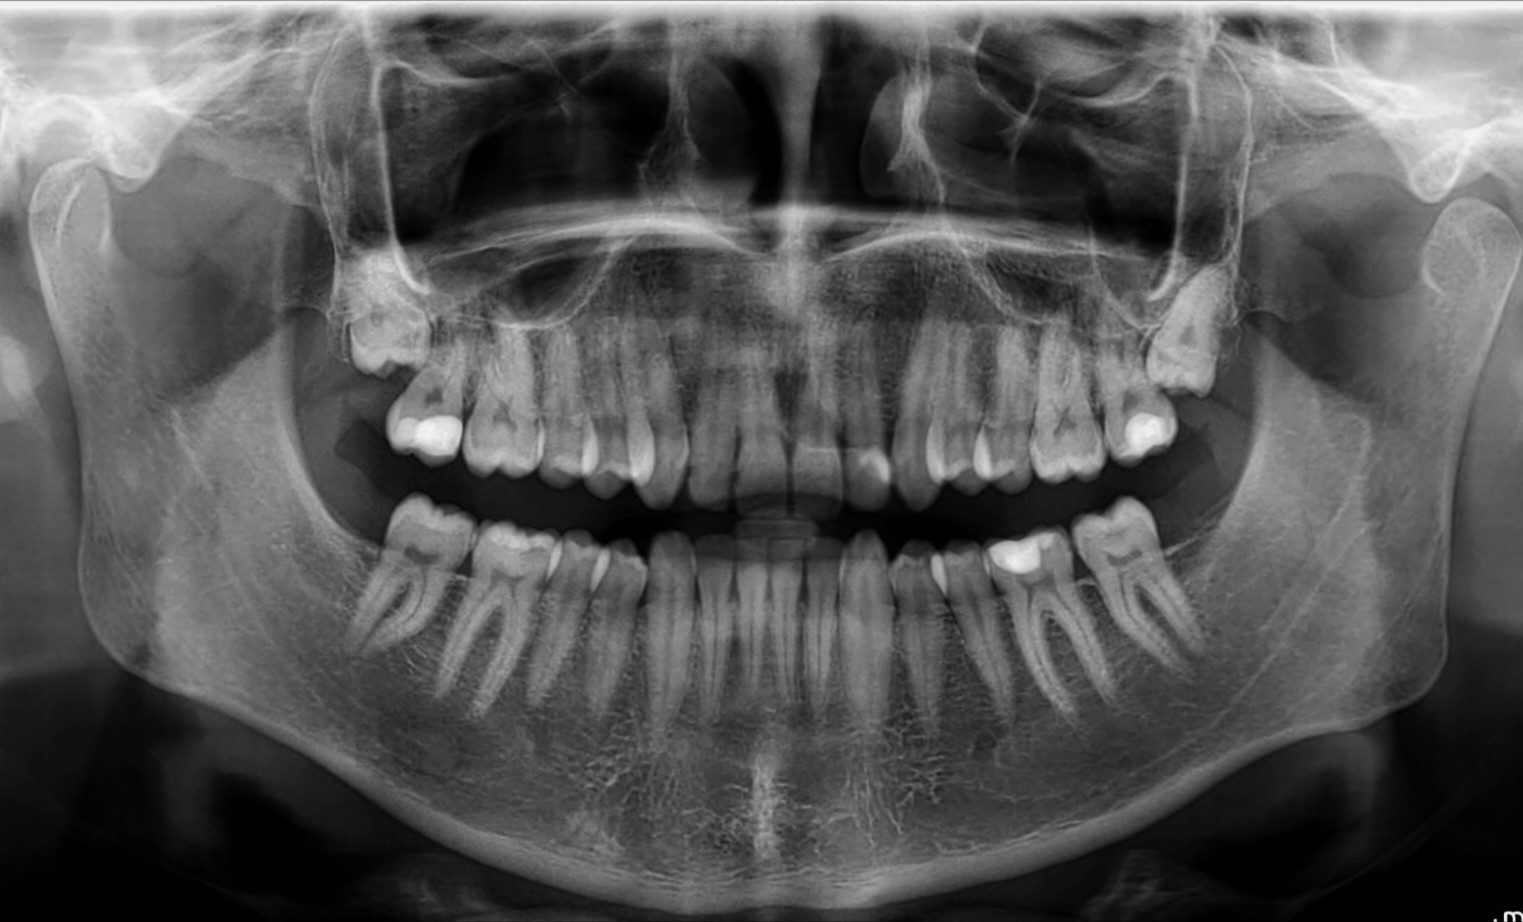

>>220892179Post the orthopantomograph

>>220892365Release the orthopantomograph files

>>220892764I don't have anything like that. I had some rengen on my teeth but it was like 5 years ago if not more

>>220892921You got a regular intraoral one then.